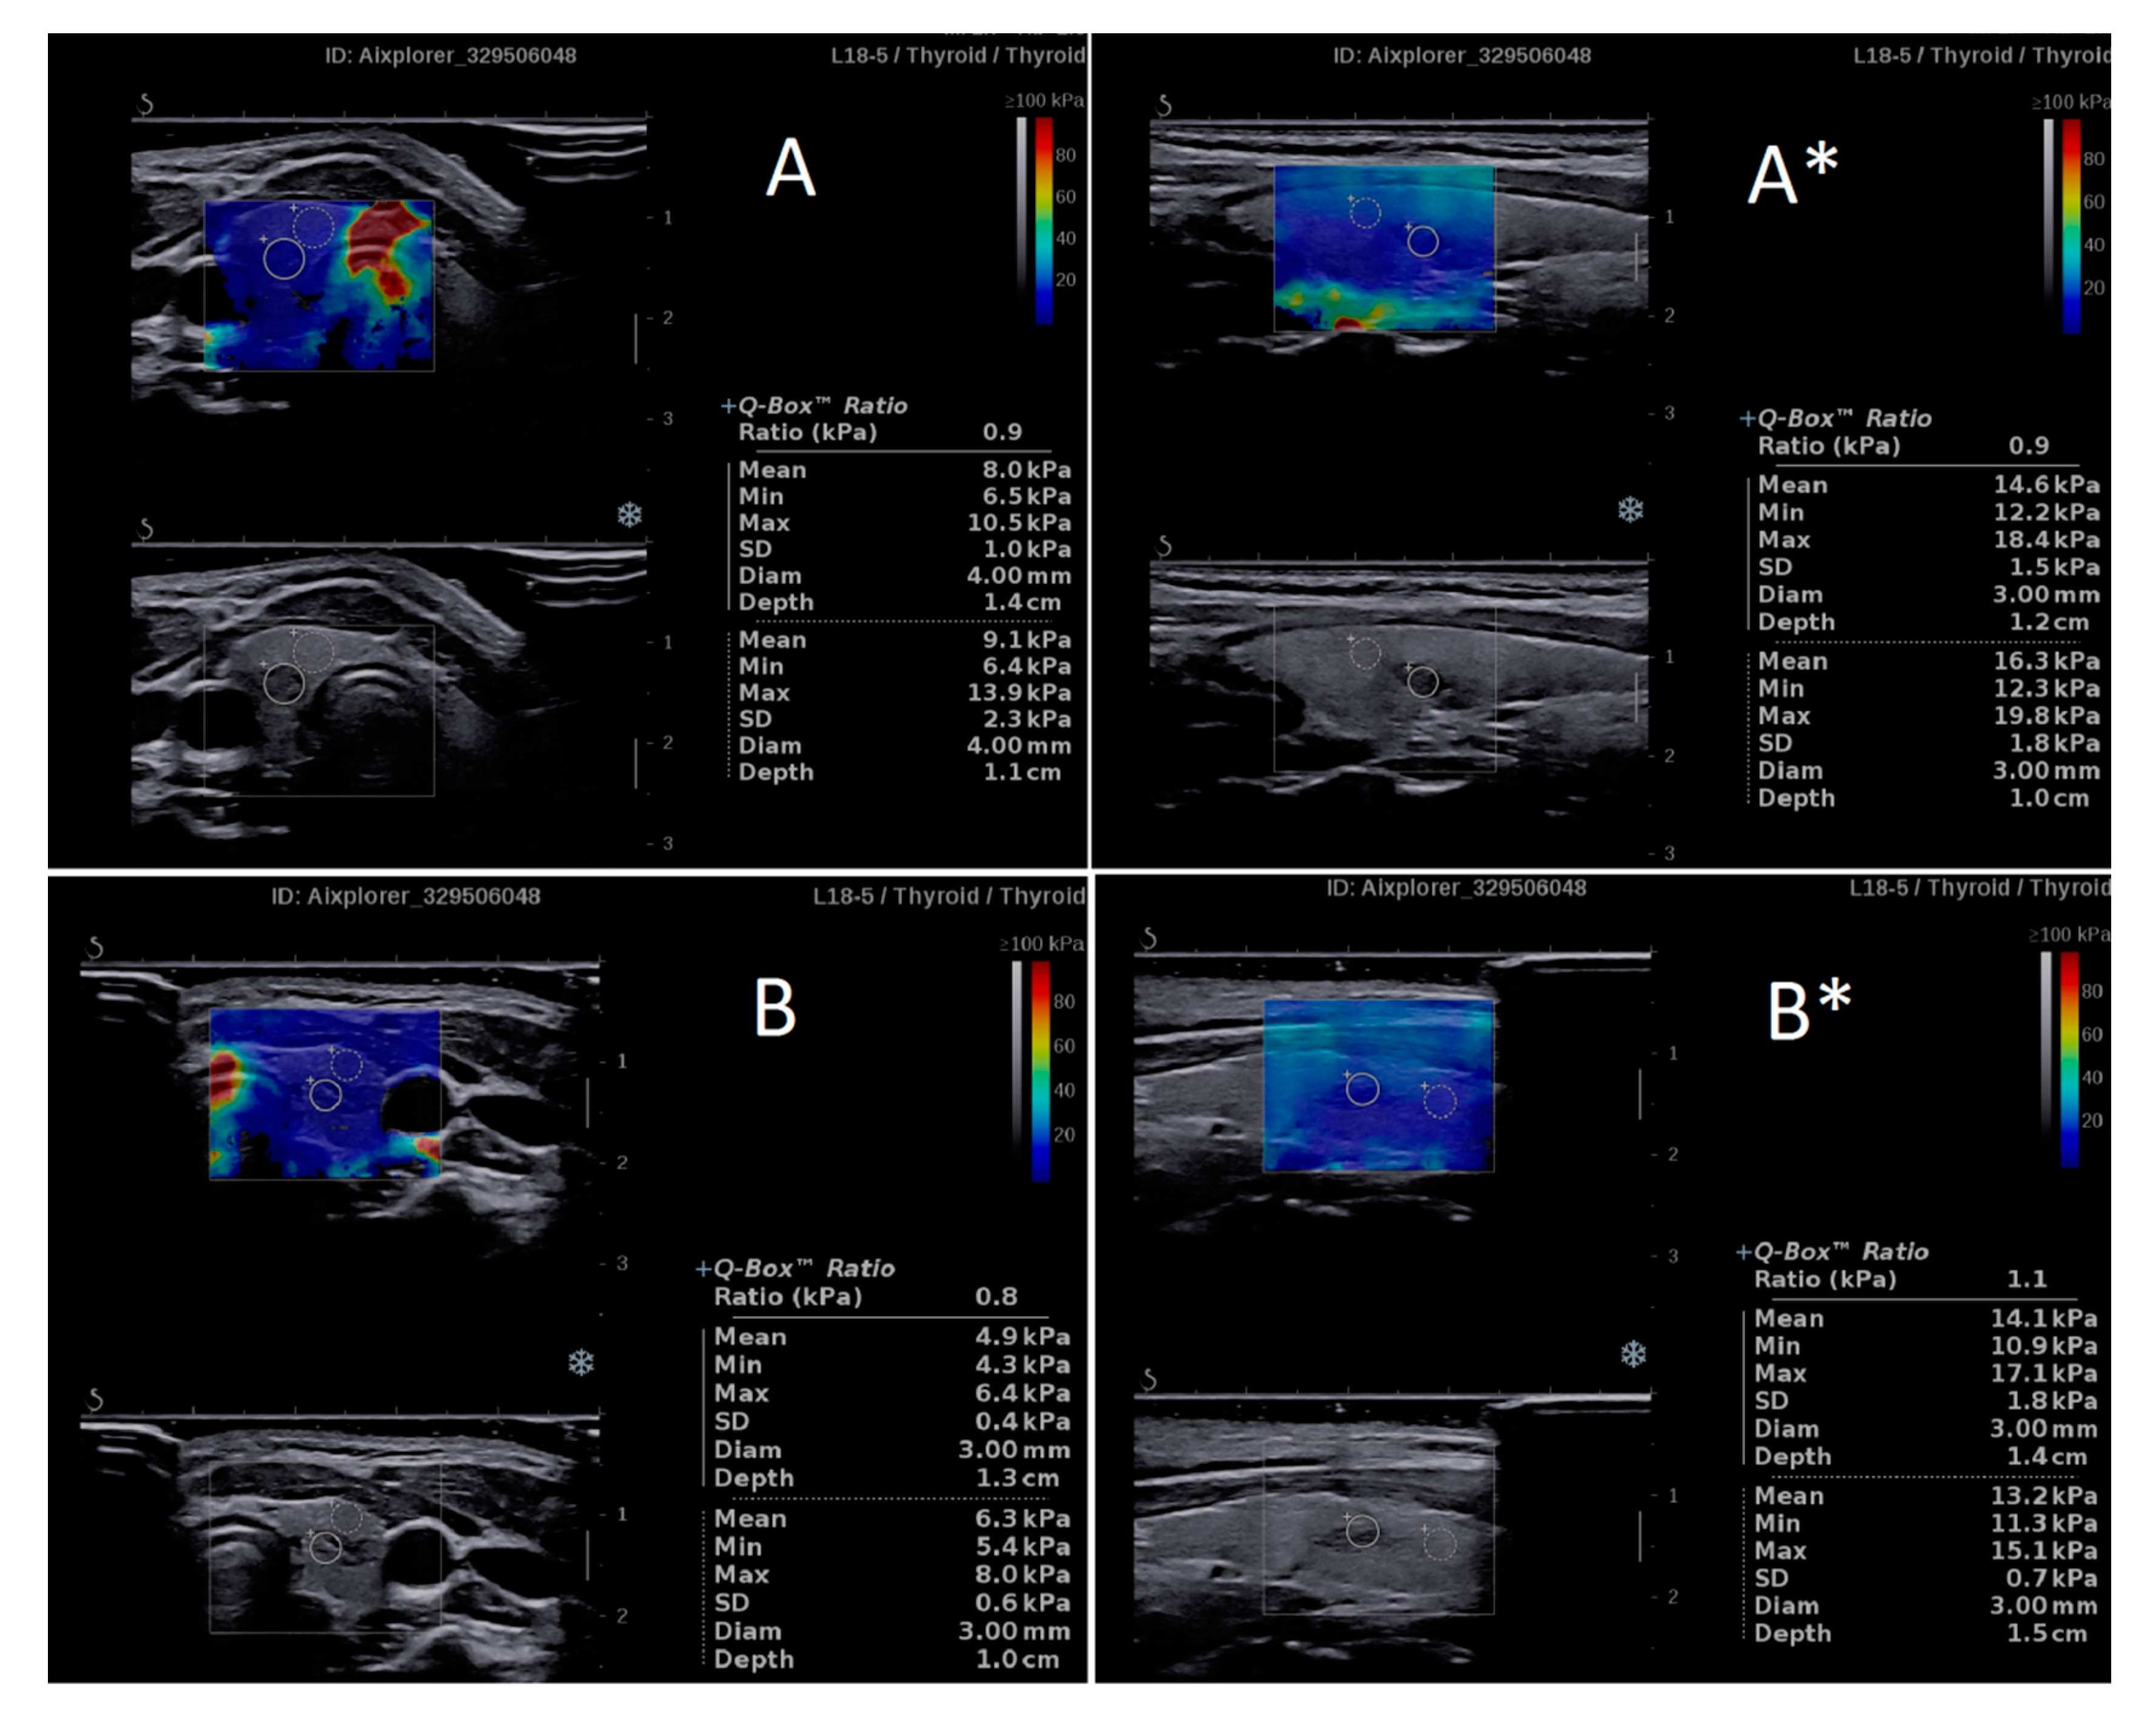

3.2. Intraobserver Variability Related to the Imaging Plane